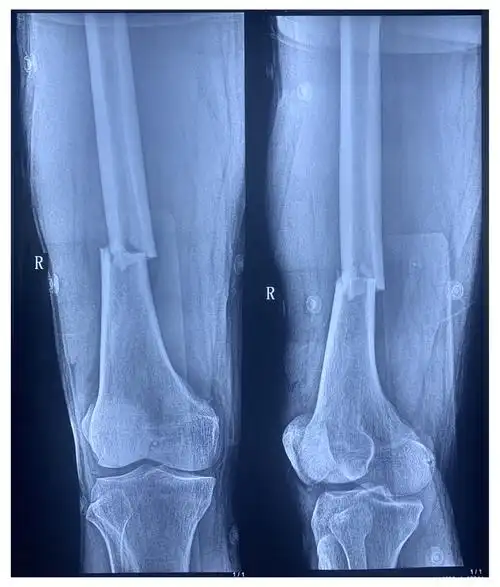

右侧股骨骨干骨折

股骨干骨折

闭合复位髓内钉治疗成人股骨干骨折